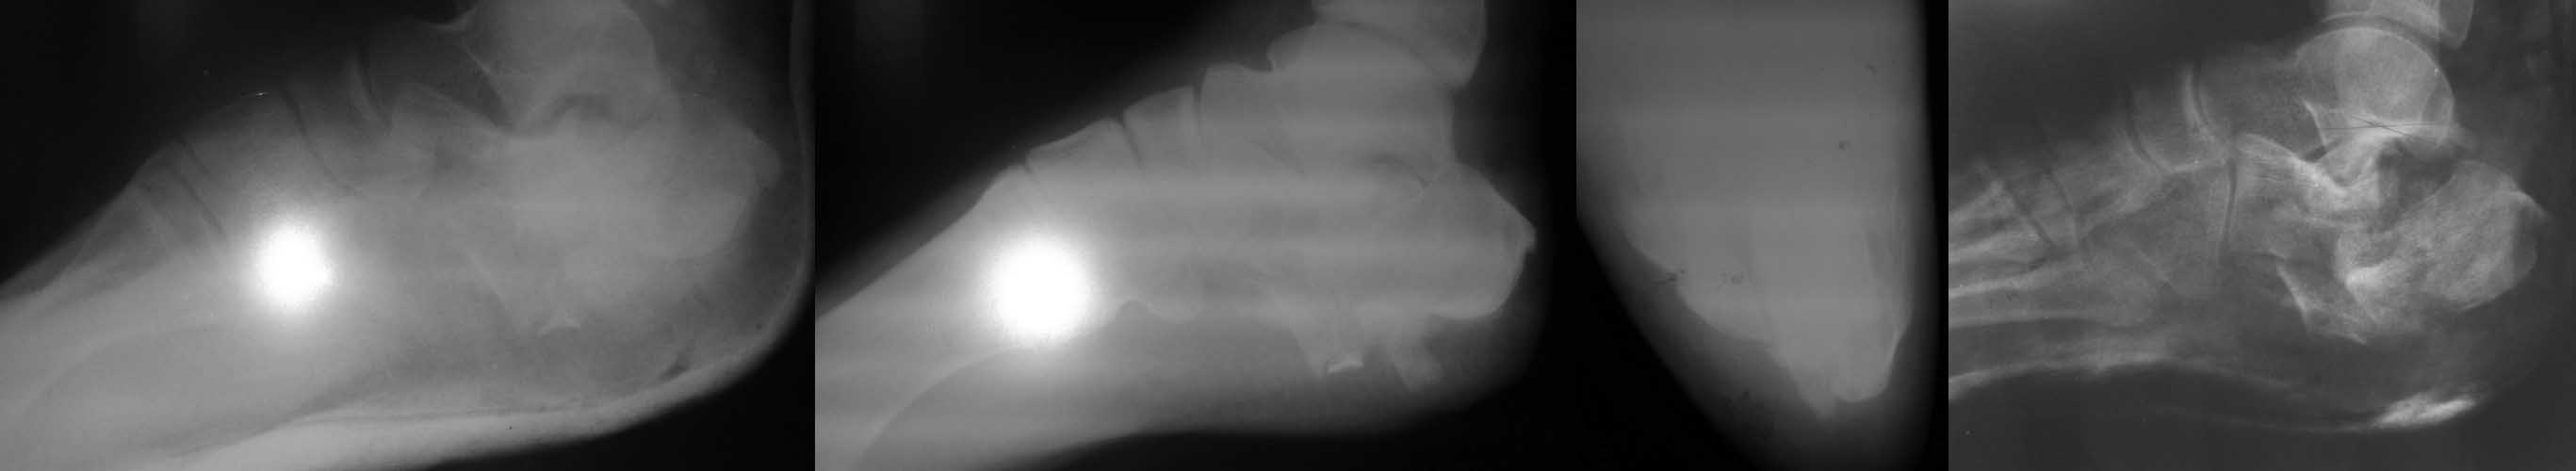

П-ка, 28 лет, выпрыгнула с 3 этажа в состоянии а/о,неосл.переломы L1,2,3,ушиб почки, мочевого пузыря, перелом пяточной кости справа без смещения, оскольчатый перелом левой пяточной кости со смещением. Rn-гр.соответственно при поступлении, контроль в динамике и после закрытой ручной репозиции под в/в анестезией. Грубое смещение сохраняется. В арсенале спицы Киршнера, возможен забор аутотрансплантата. Есть сомнения по поводу заживления( алкогольный анамнез и возможно не только)после операции. Нужно в данном случае всеми средствами приводить к более менее терпимой картине? Допустима операция после консолидации этой "каши" в отсроченном порядке или вообще консервативная тактика. Повторюсь есть сомнения в выполнении п-кой послеоперационных рекомендаций, возможно нарушение ортопедического режима? Спасибо за ваше мнение.